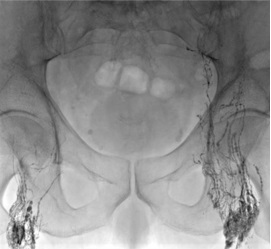

双侧经淋巴结淋巴造影

Rajebi et al, JVIR 2011 and Nadolski, JVIR 2012